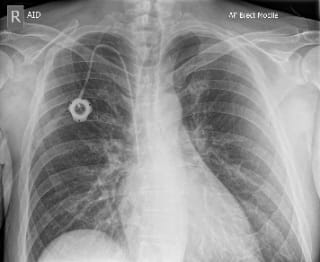

The circular thingy visible in my X-ray above is called a Portacath1, a type of implanted venous access device.

The portacath consists of two parts: a hard walled body with a silicone pad in the middle, and a flexible tube which runs inside a vein from the port location to just above the heart. Accessing these devices requires strict adherence to aseptic technique to prevent bloodstream infections especially as patients are already vulnerable.